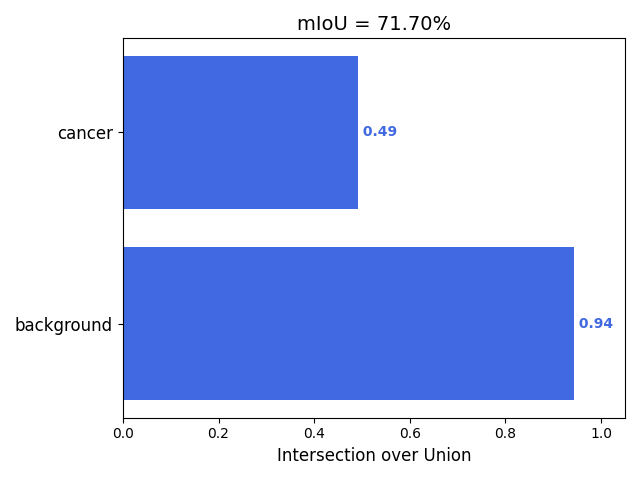

以我们的数据为例,下面是改进模型1得到的结果。